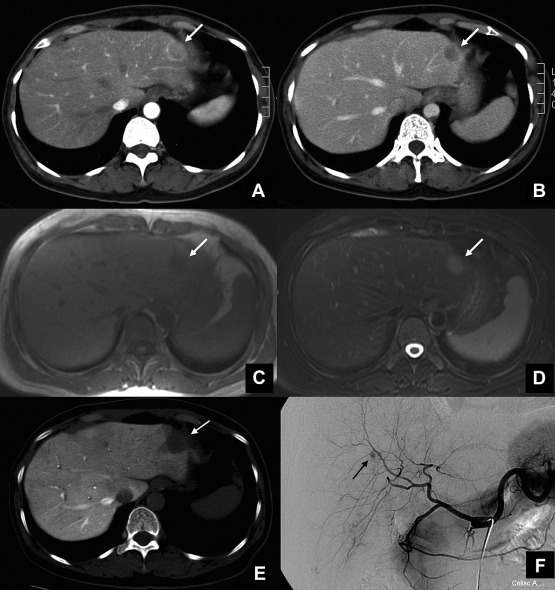

A 49-year-old woman who had a hepatic hemangioma noted since 1995 underwent an annual routine medical examination. The abdominal ultrasonography showed a hypoechoic lesion, about 20 × 16 × 14 mm in size, located in segment 2 of the liver in 2007. Laboratory tests revealed no elevation of hepatic enzymes (aspartate aminotransferase, 17 IU/L; alanine aminotransferase, 13 IU/L; alkaline phosphatase, 141 IU/L; gamma-glutamyltranspeptidase, 22 IU/L) and a normal lactate dehydrogenase level. Hepatitis B virus surface antigen and hepatitis C virus antibody were both negative. In addition, the levels of tumor markers including α-fetoprotein, carcinoembryonic antigen, and carbohydrate antigen 19-9 were all within the normal limits. The corresponding computed tomography (CT) scans revealed a relatively hypodense solid lesion with peripheral rim enhancement in arterial and portal venous phases (Fig. 1A and B). Magnetic resonance (MR) imaging showed hypointensity in axial T1-weighted images (Fig. 1C) and hyperintensity in axial T2-weighted images (Fig. 1D). Postgadolinium enhancement corresponded with the CT images. CT arterial portography demonstrated a perfusion defect in segment 2 of the liver. However, this small segment 2 tumor had no definite tumor stain on angiography study. A hypovascular tumor was impressed, and peripheral type cholangiocarcinoma, metastatic tumor, or sclerosed hemangioma should be differentiated. A left lateral sectionectomy was performed in March 2007. The patient had an uneventful postoperative course and was discharged on the 7th postoperative day.

Image findings of the lesion. (A) Abdominal computed tomography (CT) scans showed a 20-mm-diameter, slightly hypodense mass with peripheral rim enhancement in arterial phase located in segment 2. (B) Early washout of the contrast medium with retained ring enhancement was seen in the portal phase. (C) Axial magnetic resonance (MR) imaging showed a hypointense nodule on segment 2 of the liver in the T1-weighted image, and (D) the lesion became hyperintense in the T2-weighted image. (E) Arterial portography with computed tomography demonstrated a perfusion defect in segment 2 of the liver. Angiography showed a hypervascular lesion on segment 6 of the liver (arrow). (F) However, the small tumor in segment 2 of the liver on previous CT and MR had no definite tumor stain.